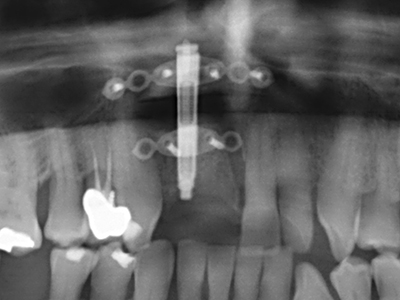

When surgical procedures are performed on bone in the immediate vicinity of sensitive structures such as blood vessels or nerves, rotary instruments pose a significant risk of iatrogenic injury. Piezoelectric devices can be helpful for preparation of bone covers and removal of hard tissue close to nerves, particularly for exposure of nerves after iatrogenic injury but also during nerve lateralization for resective and reconstructive procedures or implant placement (Fig. 17-20). Light contact between the piezotip and the nerve does not generally result in damage but proceeding incautiously with saw-like motions or attachments where a residual bone substrate remains may cause temporary or even permanent nerve damage. However, the risk of damage is considered to be substantially lower than when using saws or milling instruments (Pereira, Gealh et al. 2014).

As shown in the past, basically any bone surgery procedure represents a possible indication for piezo surgery. Thus preparation of the mobile segment in distraction osteogenesis (Fig. 23-25) and sandwich osteotomy uses special attachments without endangering the blood supply to the crestal section, which is essential for the success of both techniques (Gonzalez-Garcia, Diniz-Freitas et al. 2008).

For removal of an implant, a vestibular bone cover that is replaced after removal of the implant screw can be prepared to retain the contour of the alveolar ridge.

There are additional applications in sinus surgery. Pathologies and foreign bodies can be removed from the sinus after concentric preparation of a generally trapezoid bone cover in the facial sinus wall. The bone cover is repositioned on conclusion of the intra-antral operation component and secured by wedging or adaptive sutures to prevent dislocation.